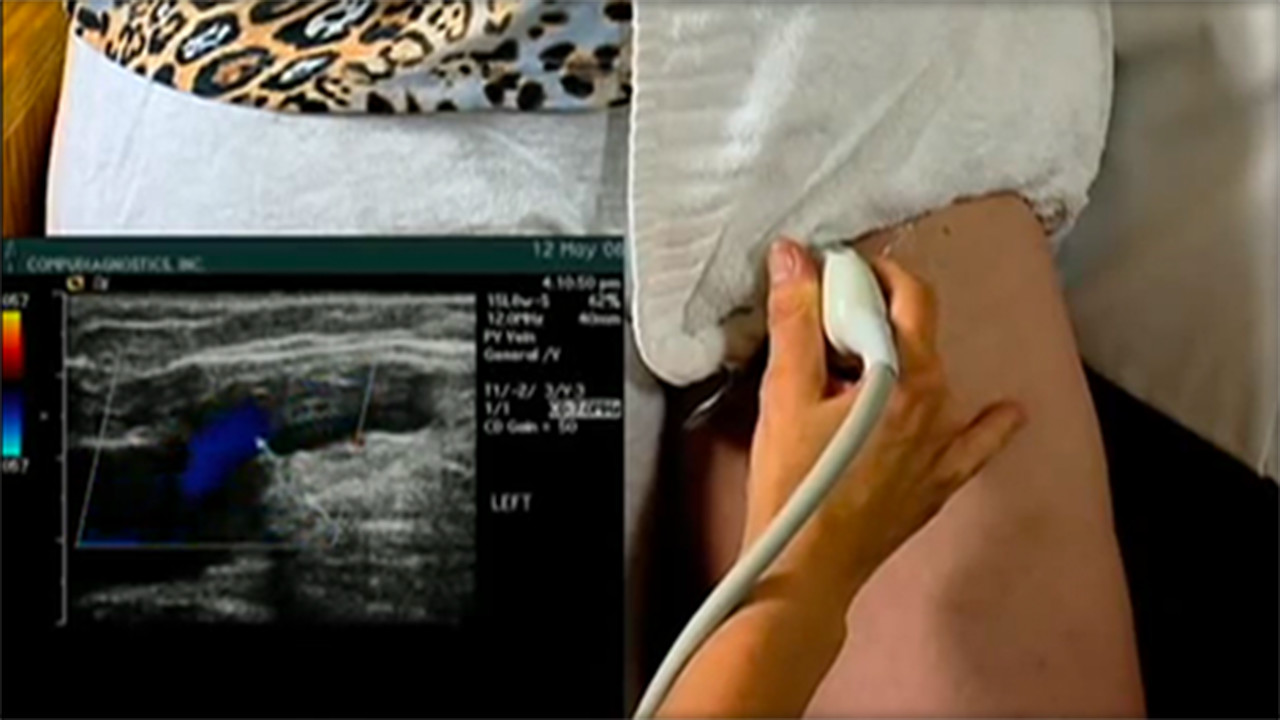

Diagnostic Procedures Superficial venous problems may be visible on the legs, but it is important to let a doctor confirm a diagnosis. Sometimes SVI can be indicative of other problems in the deep veins, such as deep venous obstruction and a doctor will need to determine if it is DVO or SVI. To confirm SVI, and to locate the source of insufficiency, a doctor may use a combination of physical exam, medical history and one or more of the following tools:5 Photos of Diagnostic Procedures

Videos of SVI Diagnostic Procedures

Duplex Ultrasound

This is a non-invasive test which uses sound waves to create a color map of the blood vessels and examines blood flow in your legs.